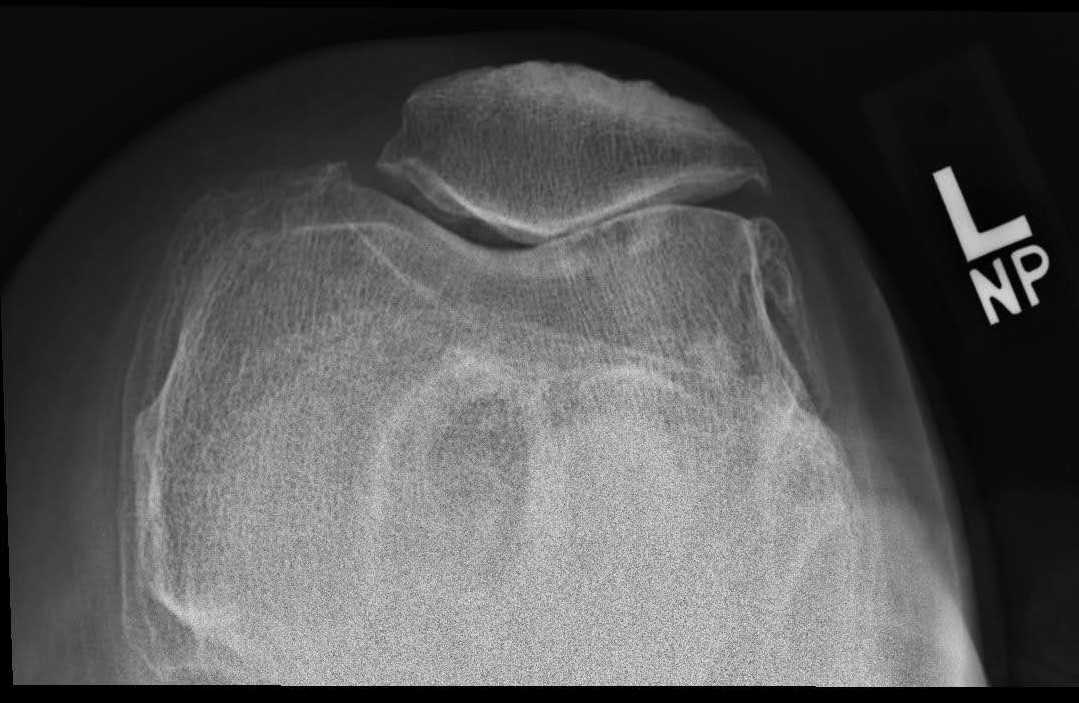

Imaging

AP weight-bearing views including bilateral knees, lateral, and sunrise views are necessary to assess knee osteoarthritis radiographically. The critical findings of knee osteoarthritis on radiologic exam are as follows:2

Finding osteophytes on x-ray best differentiates osteoarthritis from rheumatoid and other arthritides. A sensitive and specific criteria for knee osteoarthritis is the combination of knee pain, radiologic appearance of osteophytes and one or more of the following: age over 50 years, morning stiffness less than 30 minutes, or crepitus on active motion.

Bilateral weight-bearing views should be used to compare the affected with the unaffected side. Osteoarthritis should be assessed in each of the three knee compartments: medial, lateral, and patellofemoral. It should be noted that as many as 30% of adults over 65 years will demonstrate radiographic appearance of osteoarthritis, but one-third of these individuals will be asymptomatic.3 Thus, it is important to correlate clinical and radiographic findings to reach a diagnosis of symptomatic knee osteoarthritis, a clinically relevant entity.

Pre-op X-Rays

Figure 1. Pre-op x-rays.